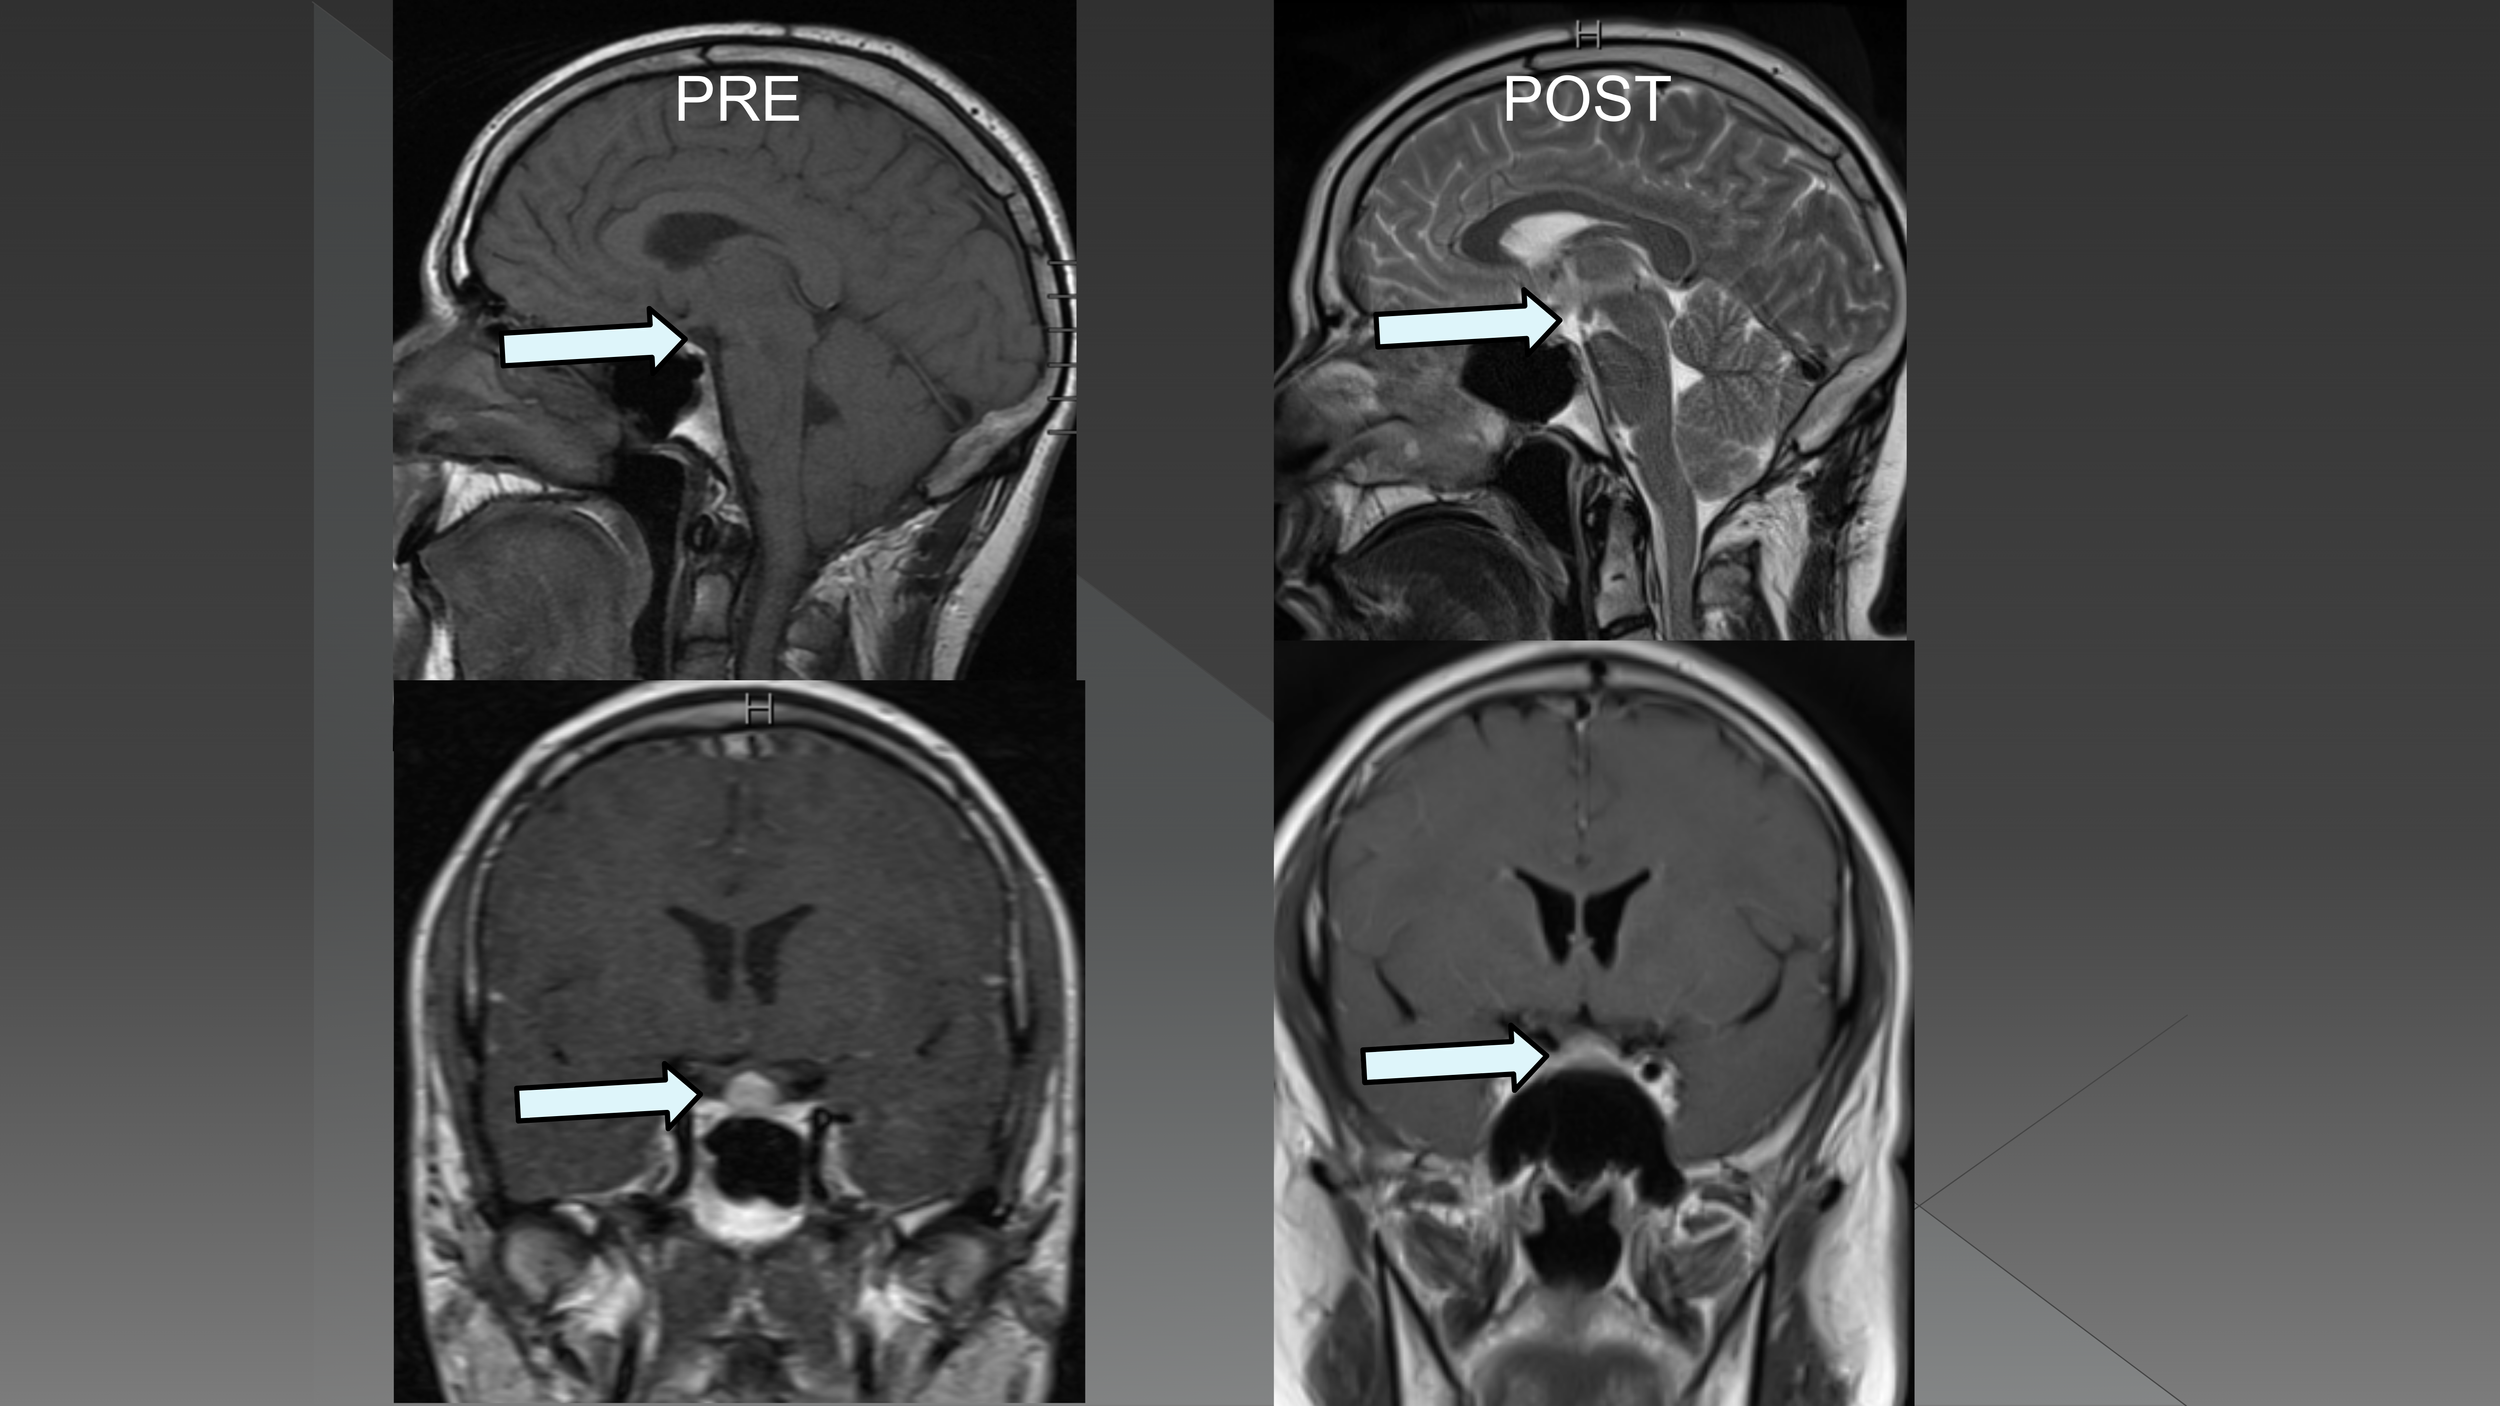

Surgical SIH treatment – a Canadian perspective - Eric Massicotte MD, MSc, MBA, FRCSC

Surgical SIH treatment - an American perspective - Wouter I. Schievink MD